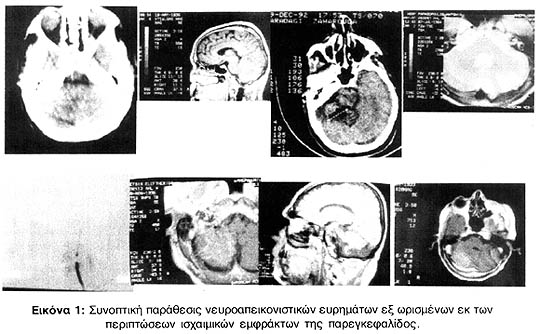

Τα νευροακτινολογικά ευρήματα των περισσοτέρων παρατίθενται συγκεντρωτικώς εις την εικόνα 1.